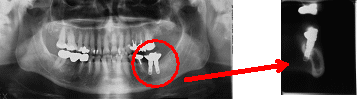

一般のレントゲンで見えなかった部分が容易に確認できるようになり、さらに正確な診断をおこなうことができるようになりました。

インプラント・矯正・抜歯など幅広い応用が可能で、治療の安全性を飛躍的に高めます。 |

それは2D撮影では写らない情報がCTなら3Dで得られるからです。

間違った診断や治療を防ぐために、近年CT撮影による情報が診断における必須になっています。 |

X線画像とは影絵の様なものなので、下の絵の人の影がX線画像だと思ってください。左手のバナナは見えますが右手のパイナップルは体と重なっていて、影では有るのか無いのか分かりません。

そこで、ライトを違う方向から当てて見るとどうなるでしょう?パイナップルが人の前にあるのが分かる影が写りました。

CTはこの原理を使用し2DX線写真で見えなかった病巣やインプラントの埋入方向などを色々な角度から見る事が出来るのです。その画像をもとに診断し患者様に分かりやすくご説明します。 |